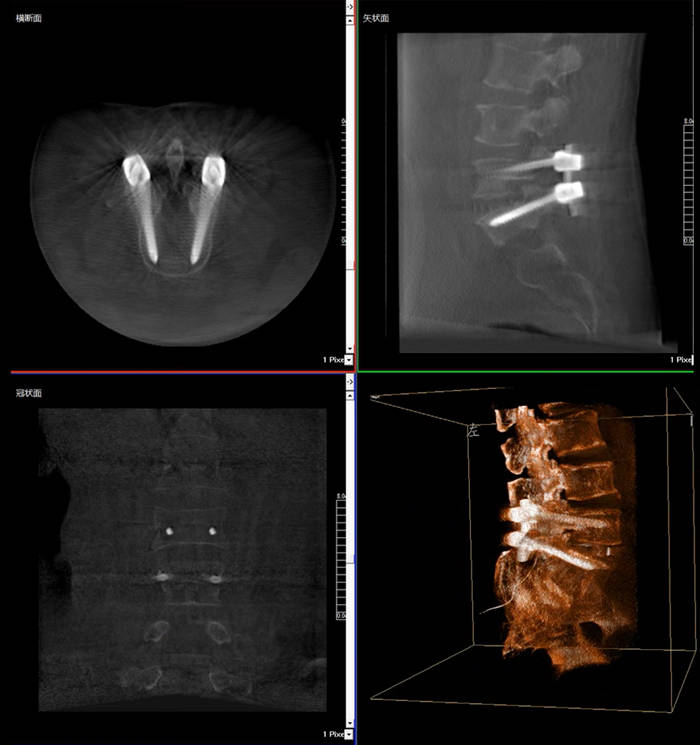

普愛醫(yī)療三維C臂X光機快速生成橫斷面、矢狀面、冠狀面斷層圖像和三維立體圖像,方便醫(yī)生確認手術部位。三維C臂X光機的大平板帶來出色的顯示視野,可以更好的顯示手術部位全局情況,確保手術規(guī)劃及執(zhí)行的準確性。

三維C臂X光機影像

普愛醫(yī)療三維C臂X光機二維、三維成像模式可快速切換,僅需30秒鐘,一鍵從二維切換至“術中CT”模式,完成術中三維圖像采集,同步生成“類CT”斷層圖像,方便醫(yī)生從各個角度各個層面來觀察病灶區(qū)域,準確定位穿刺針位置。采用30CM*30CM的動態(tài)平板探測器,成像范圍大(一次性可成像5節(jié)腰椎),無需反復透視,節(jié)約手術時間。